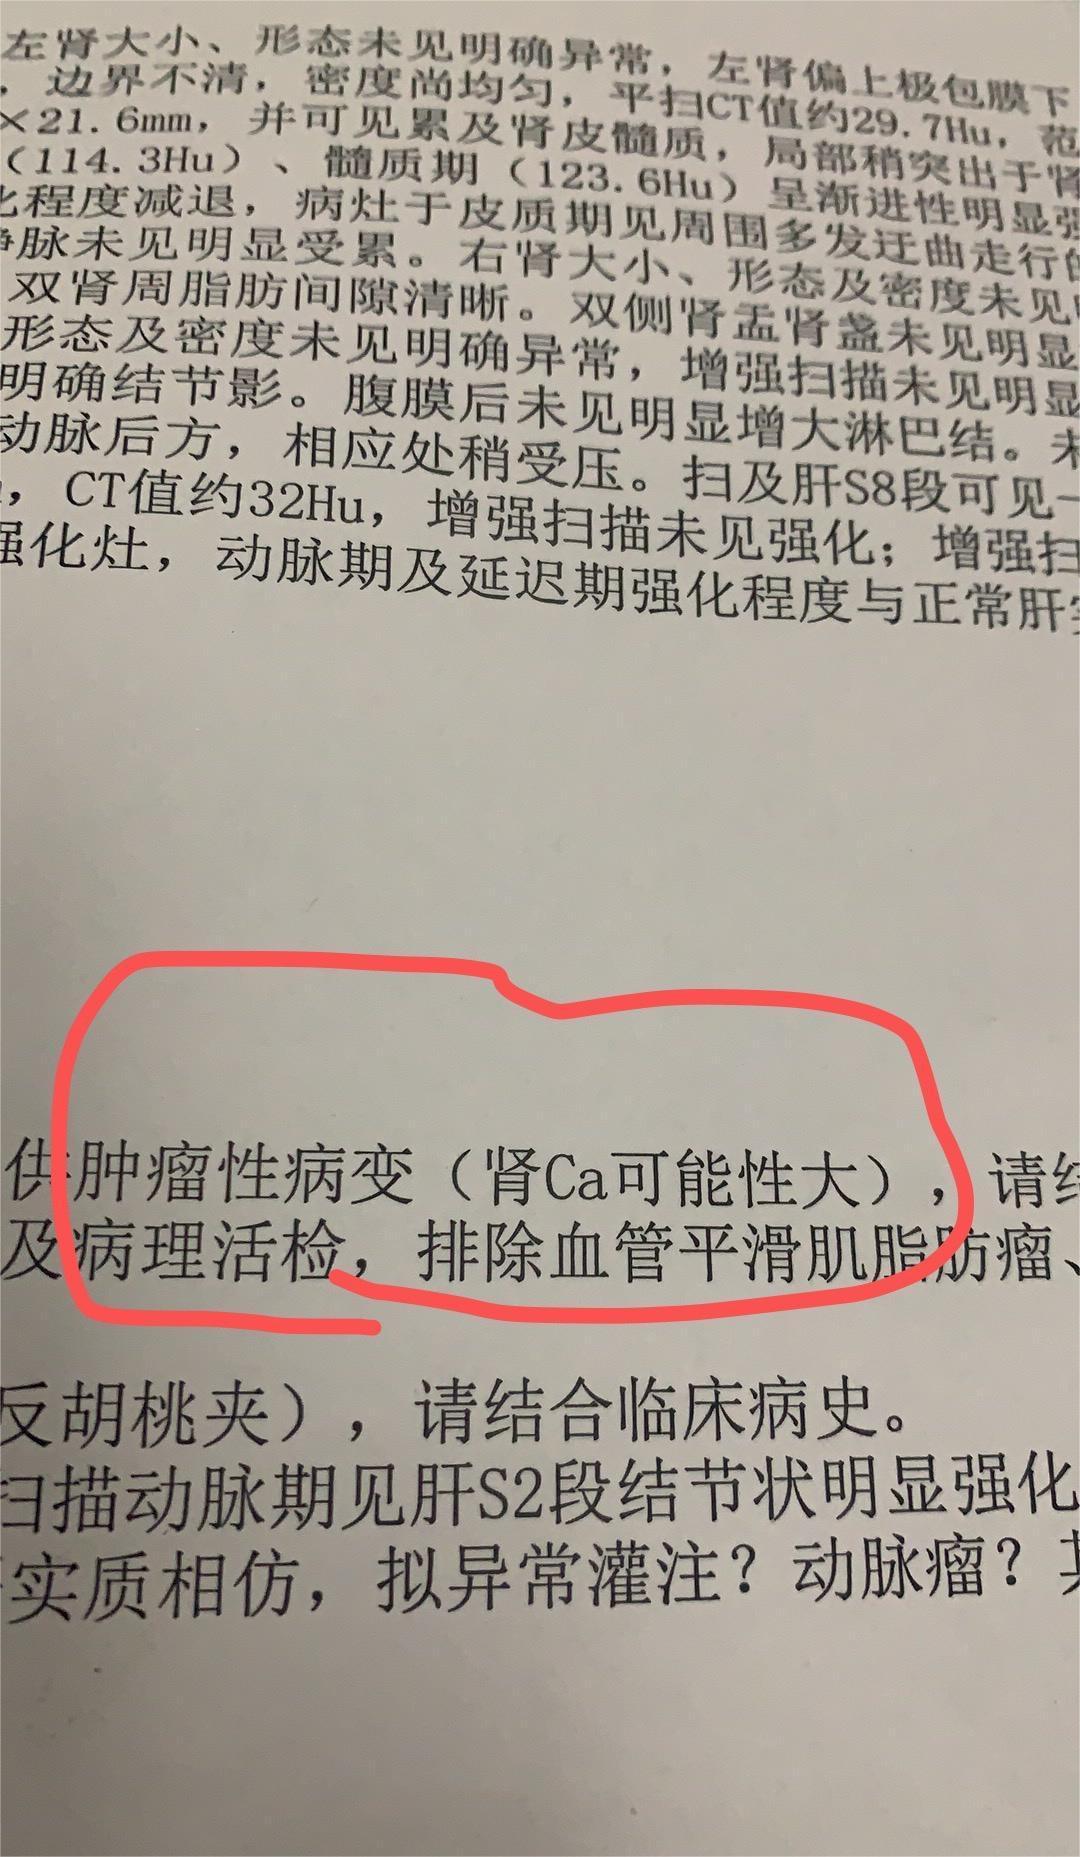

爱你的形状 02024-02-07 患者家属我2岁的女儿通过超声检查发现右肾有个肿瘤,在北京儿童医院做手术,肿瘤术中检测是小圆细胞恶性肿瘤,右肾已摘除,现在术后2天...

花谢花开花满楼 02024-01-30 患者家属 -